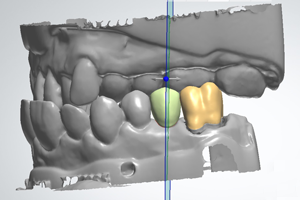

Dankzij de opkomst van CAD/CAM tandtechniek kan de tandarts bij het ontwerpen van occlusie en articulatie ook bij indirecte technieken aan het roer blijven staan.

Voorspelbare functie en esthetiek van de definitieve restauratie bij patiënten met een (ernstig) versleten dentitie vereist een gezamenlijke klinische en technische benadering door tandarts en tandtechnicus. Een systematisch concept bereik je door nauwkeurige behandelplanning met een diagnostische wax-up waarmee materiaalkeuze, preparatievorm, ‘soft-tissue management’ en tijdelijke voorzieningen worden bepaald. Tijdelijke voorzieningen spelen een essentiële rol in de communicatie tussen de patiënt en het behandelteam.

Tijdens deze lezing komen de volgende aspecten aan de orde: Esthetische en functionele analyse, behandelplanning, teamwork, materiaalselectie, CAD/CAM techniek, digitale beetbepaling, 3D gezichtsscan, moderne hoog-gevulde polymeren en volkeramiek.

Met de introductie van lithiumdisilicaat keramiek voor de enkeltands restauratie en de zeer sterke zirconiumdioxide keramieken als materiaal voor bruggen, individuele implantaat-abutments en monolitische restauraties, is de klinische toepassing van volkeramiek steeds breder inzetbaar. Sterke verbeteringen op materiaalgebied en toegenomen kennis van de eigenschappen van zirconiakeramiek in combinatie met digitale afdruk- en tandtechniek zorgen voor een verhoogde betrouwbaarheid en betere esthetische resultaten in posteriere restauraties. Echter een adequaat occlusaal concept blijft de grondslag voor de levensduur van de restauratie.